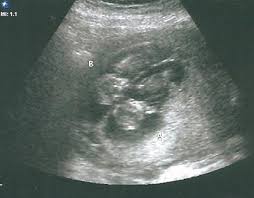

At the end of this week, lines can be spotted on their fingertips. Estimated fetal weight for twins fetal growth chart fetal weight chart full term for twins twin fetal growth chart twin pregnancy week by week twin pregnancy: If your nausea and vomiting is super severe, definitely bring it up to your ob. That's because twin moms can have more of the pregnancy hormone hcg in their systems. What would 13 weeks pregnant feel like? Sep 26, 2018 · the second trimester is officially on once you are 13 weeks pregnant. If you're 13 weeks pregnant with twins, you might still be experiencing some morning sickness and fatigue. Your complete guide twin weight chart.

These facts are not only from over 10 years of experience being the #1 twin parenting website online, but some of the info is literally taken from our over 1 million parent audience. Their lungs are well developed by 34 weeks. Nevertheless, make the best of what you can and enjoy the luxury of pregnancy. From week 8 to 12, the last month representing the embryonic stage, your twins are swiftly progressing in their development they will have quadrupled in both length and weight. Twin pregnancy symptoms and conditions. Lowest prices from hundreds of sites all in one place. Your babies are approximately 7,5 cm (2.95 inches) from head to rump when you're 13 weeks pregnant with twins. 2697 grams / 5lbs, 15oz. Sep 26, 2018 · the second trimester is officially on once you are 13 weeks pregnant. The first trimester is the first three months or until 13 weeks pregnant with twins. When do you start showing with twins? The average newborn twin weighs 5 1/2 pounds. Your complete guide twin weight chart.

3261 grams / 7lbs, 3oz. Nevertheless, make the best of what you can and enjoy the luxury of pregnancy. How did you feel at 13 weeks? As well as the pregnancy symptoms being more severe, they can also occur much earlier on. All your children's organs are developed but are still maturing. Women who are carrying twins or multiples in their wombs tend to have it a tad more difficult than those who are pregnant with a single baby. From week 8 to 12, the last month representing the embryonic stage, your twins are swiftly progressing in their development they will have quadrupled in both length and weight. Estimated fetal weight for twins fetal growth chart fetal weight chart full term for twins twin fetal growth chart twin pregnancy week by week twin pregnancy: 2697 grams / 5lbs, 15oz. What would 13 weeks pregnant feel like? 3089 grams / 6lbs, 12oz. Sep 26, 2018 · the second trimester is officially on once you are 13 weeks pregnant. Twin pregnancy symptoms and conditions.